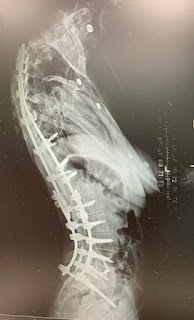

Hope just woke up after a 3 hour sleep!  Yeah!  I'm going to go try to find a place to heat up her supper, if possible.  So, I'll quickly finish this up, but will post later as I'm going to try to add pictures of her x-rays to show you the new hardware . . . it's quite the sight!

The photo on the left is the AFTER picture that shows the two repaired rods, each with a cut away section and then the added on pieces, as well as the extra screws.

This side view blows me away to see how big those screws are!

This view also shows the significant kyphosis or forward position of Hope's neck.  This will continue to be monitored by her spinal surgeon, and although it causes a lot of pain and makes swallowing more difficult, the surgeon feels the risks outweigh the benefits in this surgery at present.  That would only change if the vertebrae start to slip and pinch the spinal cord more significantly.  Right now there is pressure on the spinal cord, but it is not pinched.